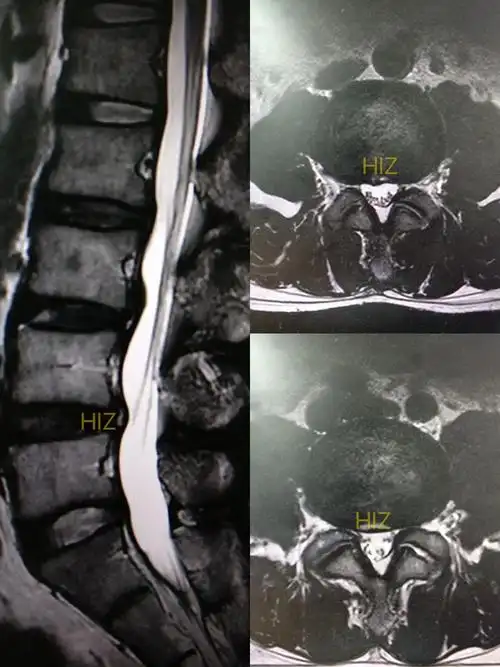

mri平扫图片示明显的腰椎间盘突出(图片来自上海中山医院)